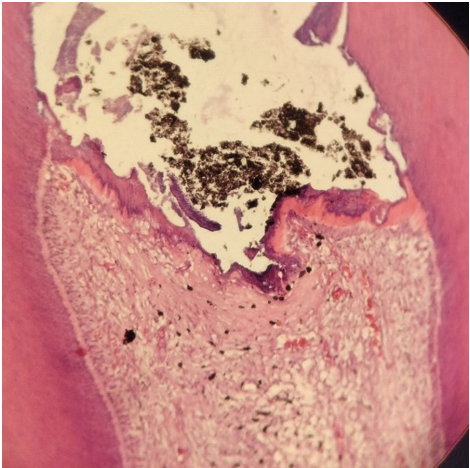

本研究针对直接盖髓(DPC)治疗中材料选择的难题,研究人员开展了四种生物活性材料(Neo MTA Plus、Neo Putty、TotalFill BC RRM Fast Set Putty和TotalFill BC RRM Paste)的短期组织学对比研究。通过双盲随机交叉设计,发现Neo MTA Plus组牙髓炎症强度(PII)最低,而Fast Set Putty组牙本质桥连续性(DBC)最佳。该研究为临床DPC材料选择提供了关键组织学依据,发表于《Scientific Reports》。